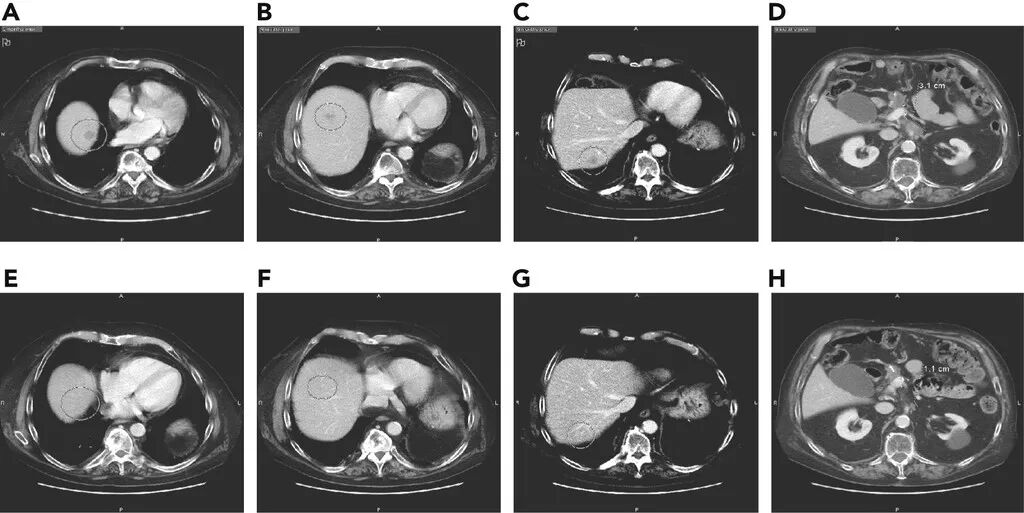

近日,美国国家综合癌症网络(NCCN)上报道了一款非常振奋人心的新药物,为癌症患者带来了生存的希望!一位81岁高龄的晚期胰腺癌患者,在接受了手术、化疗后病情不断进展,临床上已经没有标准治疗方案,在接受了拉罗替尼治疗后,病灶竟然全部奇迹消失!